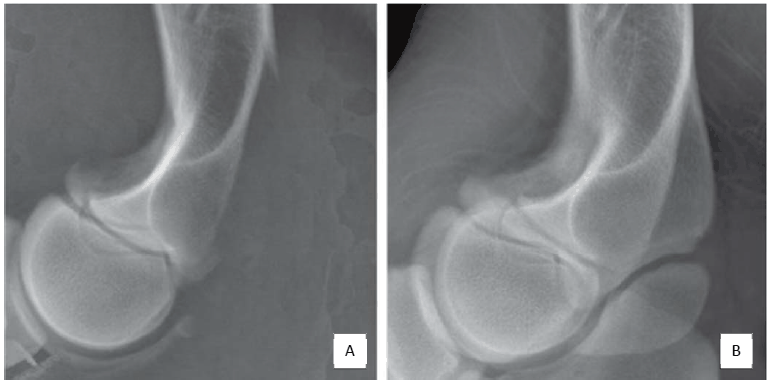

Observe as imagens seguintes.

A subexposição e a superexposição de exames realizados em equipamentos digitais resultam em uma aparência e interpretação da imagem diferente da subexposição e superexposição provenientes de equipamentos analógicos, a exemplo das imagens acima (imagens A e B correspondem ao mesmo animal e à mesma estrutura com técnicas radiográficas digitais diferentes) em que a técnica utilizada modificou algumas informações anatômicas da porção distal do úmero. Para estas imagens, esse efeito é proveniente da